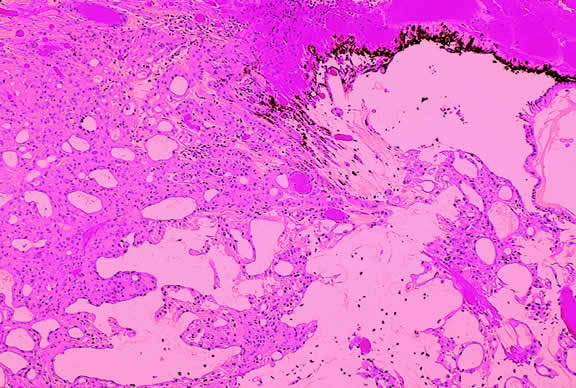

Lymphoma

Although non-Hodgkin's lymphoma often affects the orbit and conjunctiva, intraocular involvement by lymphoma is relatively rare and occurs in two basic ways. First, patients who have widely disseminated systemic lymphoma may develop secondary ocular involvement whose typical manifestation is uveal infiltration. Second, in the variant of central nervous system (CNS) lymphoma that has been called primary lymphoma of the CNS and retina, the vitreous characteristically is involved and the uvea is spared. The latter entity also has been called vitreous large cell lymphoma or ocular “reticulum cell sarcoma.”205–208 In addition to the vitreous, the lymphoma cells also infiltrate the retina, and typically collect between Bruch's membrane and the retinal pigment epithelium, forming solid yellowish RPE detachments, which are highly suggestive of the diagnosis. This rare variant of primary CNS lymphoma should be suspected in older patients who have chronic vitritis that is unresponsive to therapy. Cytologic examination of diagnostic vitrectomy specimens reveals a highly cellular and extensively necrotic infiltrate that contains atypical lymphocytes with prominent nucleoli and protrusions of the nuclear membrane (Fig. 53). The significance of elevated vitreous interleukin 10 levels as a diagnostic marker for lymphoma is controversial.209,210

Fig. 53. Primary central nervous system lymphoma, vitreous. Diagnostic vitrectomy specimen contains large atypical lymphocytes, necrotic lymphoid cells, and nuclear debris. Lymphoma cells in inset have nuclear membrane protrusions and prominent nucleoli. Main figure, Millipore filter. (Hematoxylin-eosin, × 250.)

Many patients who undergo diagnostic vitrectomy to exclude lymphoma actually are found to have a form of granulomatous vitreitis termed idiopathic senile vitritis.211 Cytologically, the latter lacks necrosis and contains a mixture of well-differentiated lymphocytes and epithelioid histiocytes with a spindled or dendritiform configuration. Careful cytologic screening and follow-up are warranted in such cases, however, because vitreous lymphoma occasionally presents with chronic inflammation. Imaging studies and spinal fluid examination should be performed to exclude CNS involvement if vitreous lymphoma is diagnosed.206 CNS lymphoma may produce dementia and other neurologic signs. The prognosis is poor with a mean survival of 22 months. Intraocular Whipple's disease may mimic vitreous lymphoma.212,213

The vitreous usually is spared when disseminated, non-CNS, non-Hodgkin's visceral lymphomas involve the eye secondarily (Fig. 54). Such lymphomas usually involve the uvea, but vitreous infiltration does occur sporadically. Occasional patients with intraocular lymphoma may present with iris heterochromia or a pseudo-hypopyon of lymphoma cells.

Fig. 54. Secondary choroidal involvement by disseminated large cell non-Hodgkin's lymphoma. Eye was obtained postmortem. (Hematoxylin-eosin, × 100.)